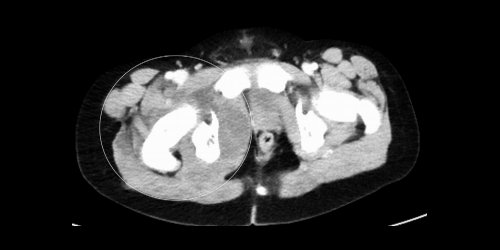

🧫JASPI Case Report (Vol. 3 Issue 4) 🦠MRSA Pyomyositis in Chronic Granulomatous Disease. 📌CT: Multiloculated gluteal & thigh abscesses. 🔬Culture: MRSA. 💊Treated with drainage + targeted antibiotics. 🔗 doi.org/10.62541/jaspi… #MRSA #ICMRDelhi #Pyomyositis #InfectiousDiseases

📌CT: Multiloculated gluteal & thigh abscesses.